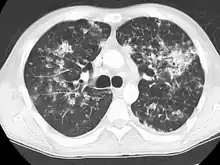

A case of miliary tuberculosis in an 82-year-old woman:

CT, 16 days after onset, showing extensive pulmonary parenchymal involvement consisting of irregular septal thickenings with ground-glass areas and centrilobular nodules with a peri-lymphatic distribution